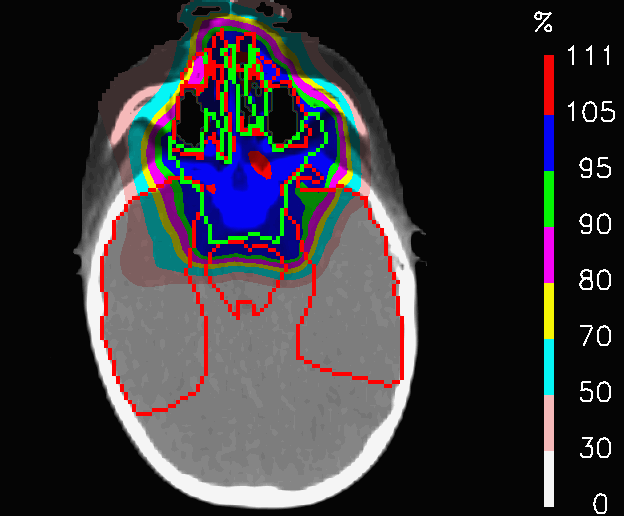

In Fig.7, the dose distributions of PLAN-NOM and PLAN-OL-1 are shown, but it is from tables 1 that we get an insight regarding the main differences of the plans. In PLAN-OL-1, the dose coverage of the clinical target volume (CTV) improves significantly leading to an increase of +5.4% of the volume reached by 100% of the prescribed dose (𝐕𝟏𝟎𝟎subscript𝐕100\mathbf{V_{100}}). Moreover, left and right parotis, the myelon and the brainstem are characterized by a substantial decrease in both the maximum and the mean dose (𝐃𝐦𝐚𝐱subscript𝐃𝐦𝐚𝐱\mathbf{D_{max}}, 𝐃𝐦𝐞𝐚𝐧subscript𝐃𝐦𝐞𝐚𝐧\mathbf{D_{mean}}) in PLAN-OL-1. The improved sparing of the parotis is well represented by the comparison of the cumulative DVHs in Fig.8, where the red line refers to PLAN-NOM and the blue one to PLAN-OL-1.

Refer to caption

(a) PLAN-NOM

(b) PLAN-OL-1

Figure 7: Patient with metallic cage: dose distributions for the nominal plan and the one re-computed with OL penalization, keeping the same field configuration.